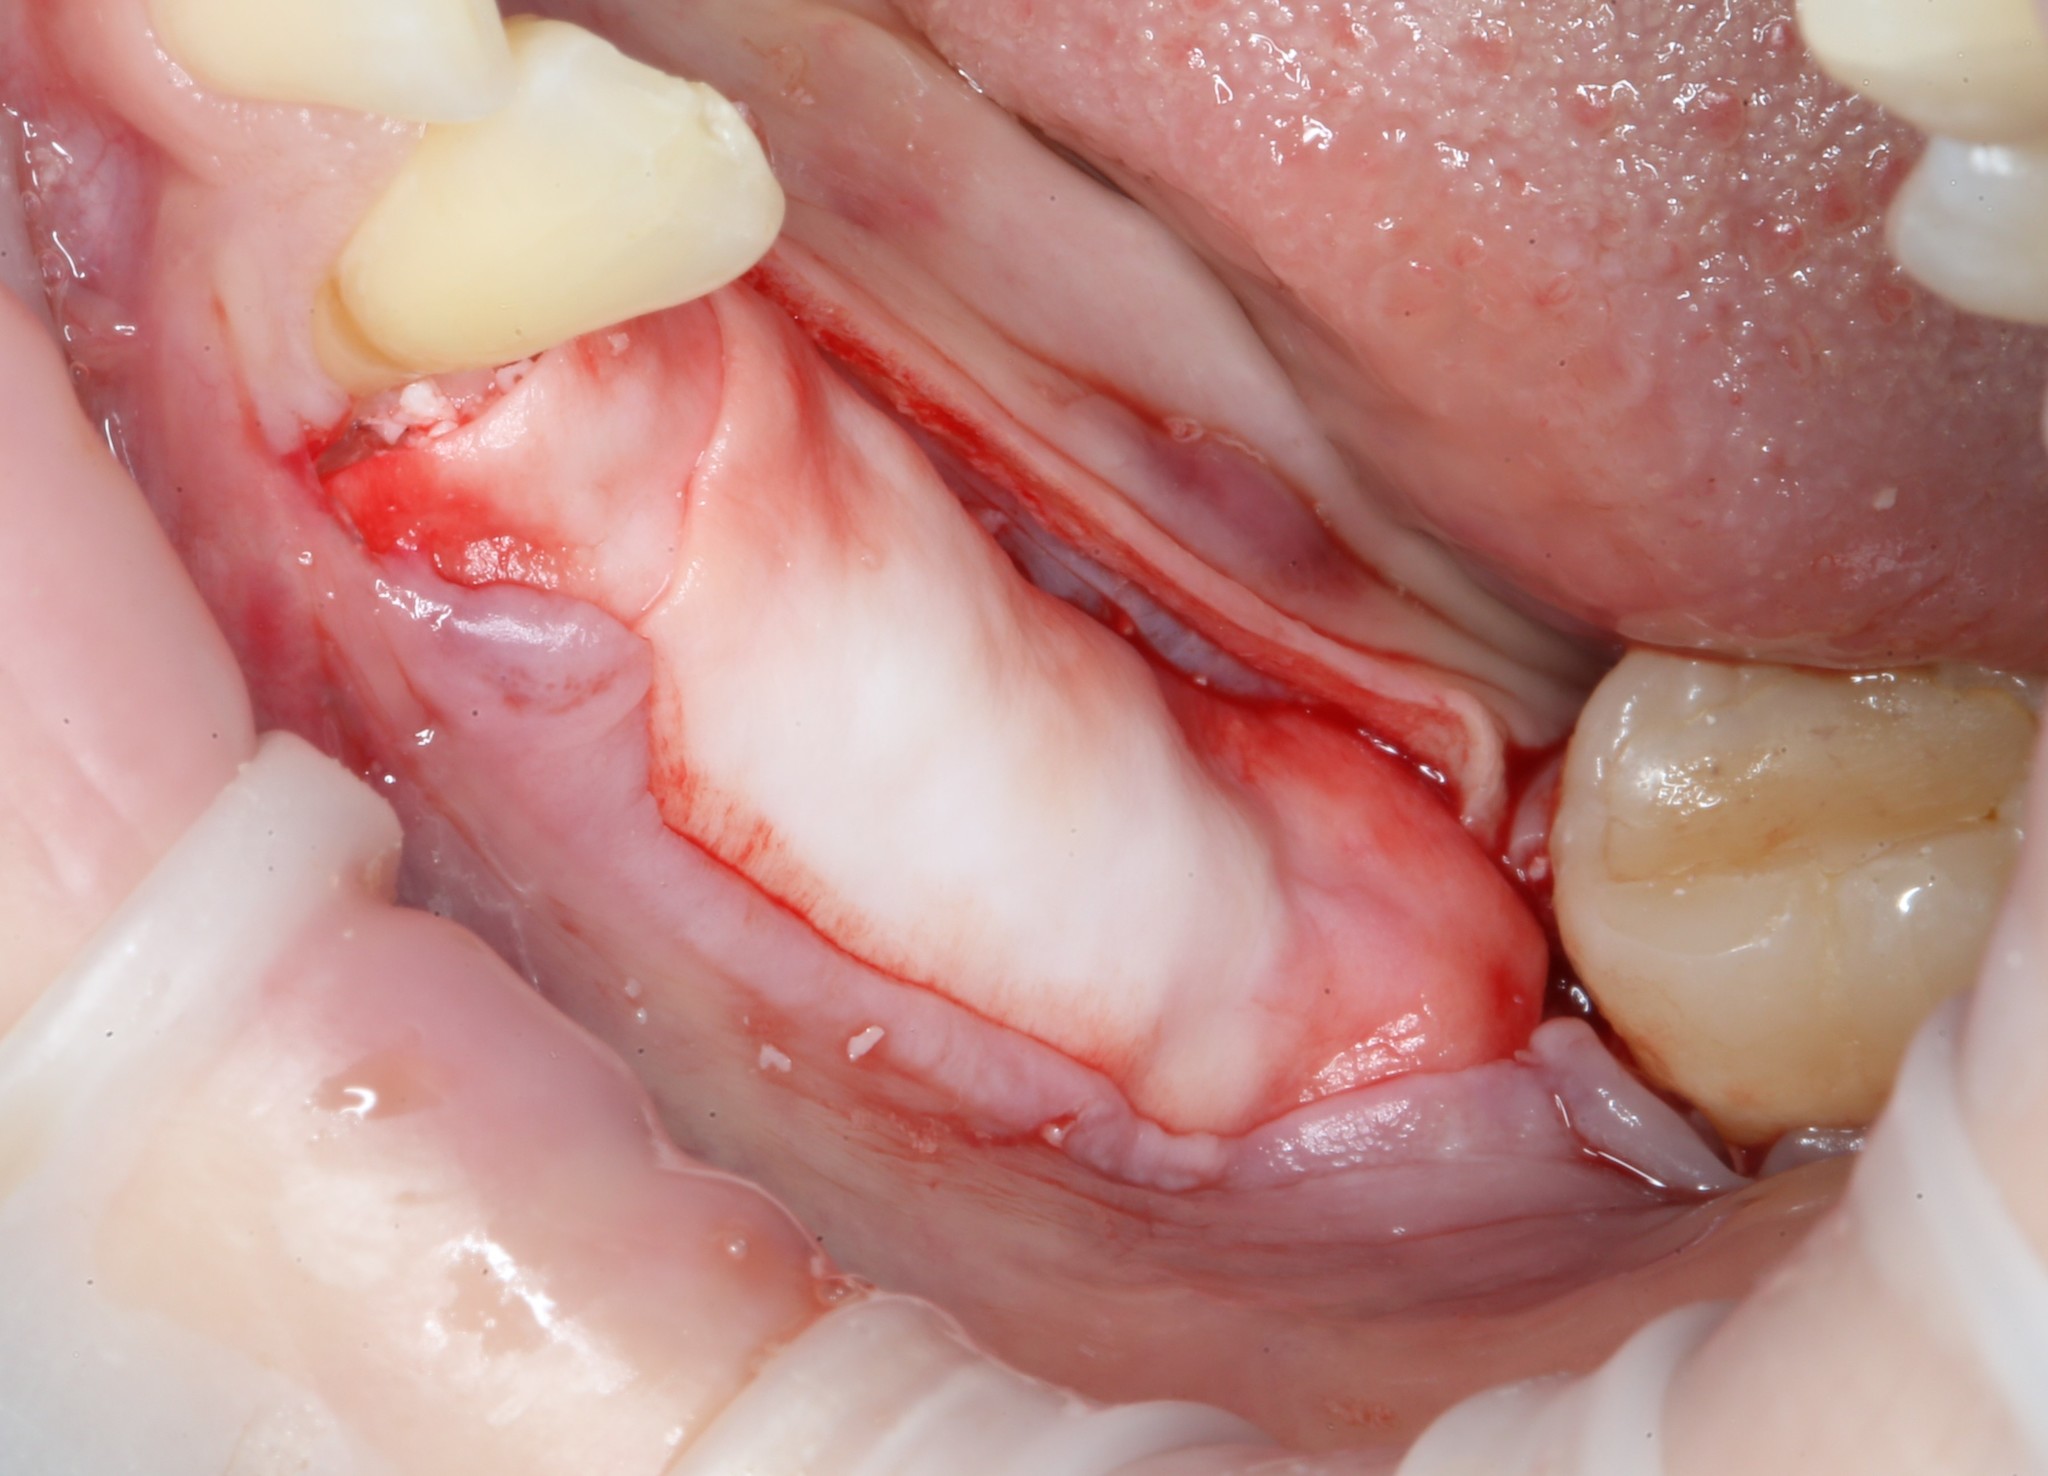

Всё тот же разрез и скелетирование кости:

Фиксирующие винты нам больше не нужны. Неровные костные края сошлифовываются при помощи того же прямого наконечника, но уже с твёрдосплавными шаровидными борами:

Выглядит это так: